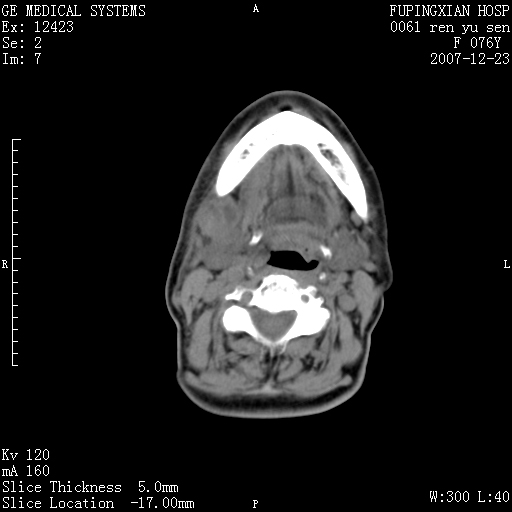

男性 76岁 下颌右侧磨牙区肿物数月, 约2.0*1.5cm大小波及颊舌侧,伴颌下淋巴结肿大。余(-)

右颈部颌下腺前可见一类圆形软组织密度影,密度不均,内见小片坏死区.颌下颈前可见两枚肿大淋巴结影.考虑淋巴结感染可能性大,建议增强扫描..

左侧声带是否突出 请关注

喉癌?转移?是否*应考虑

右侧第四磨牙缺失,局部牙槽骨质破坏,边界欠清晰,同侧颌下及竟不见多发肿大淋巴结显示。考虑肿瘤病变可能性大,感染待排

为什么都考虑感染性病变?转移性淋巴结肿大?淋巴瘤?